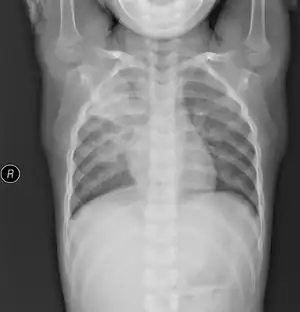

Mycoplasma pneumonia (also known as "walking pneumonia") is a form of bacterial pneumonia caused by the bacterial species Mycoplasma pneumoniae. It is also known as PPLO, which is an acronym for Pleuro Pneumonia Like Organism.

Mycoplasma pneumoniae is spread through respiratory droplet transmission. Once attached to the mucosa of a host organism, M. pneumoniae extracts nutrients, grows, and reproduces by binary fission. Attachment sites include the upper and lower respiratory tract, causing pharyngitis, bronchitis, and pneumonia. The infection caused by this bacterium is called atypical pneumonia because of its protracted course and lack of sputum production and wealth of extrapulmonary symptoms. Chronic Mycoplasma infections have been implicated in the pathogenesis of rheumatoid arthritis and other rheumatological diseases.

M. pneumoniae infections can be differentiated from other types of pneumonia by the relatively slow progression of symptoms. A positive blood test for cold-hemagglutinins in 50–70% of patients after 10 days of infection (cold-hemagglutinin-test should be used with caution or not at all, since 50% of the tests are false-positive), lack of bacteria in a Gram-stained sputum sample, and a lack of growth on blood agar.